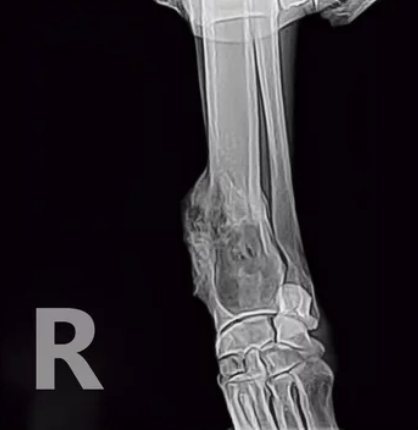

우선 강아지 관절염은 소량의 관절 액체를 채취하여 임상실험 및 방사선 촬영을 활용하여 진단받을 수 있습니다. 또한 X-ray도 관절의 손상도를 알아볼 수 있어 관절염을 진단하는데 도움이 됩니다. 이러한 검진 이전에 평소 생활에서 다음과 같은 행동을 보이면 관절염의 증상으로 의심해 볼 수 있습니다.